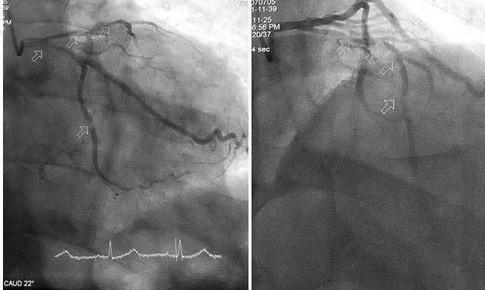

Hợp tác quốc tế trong lĩnh vực tim mạch, can thiệp thành công 4 ca bệnh khó

Y tế - 21/09/2025 10:10SKĐS – Các chuyên gia của Bệnh viện Đa khoa tỉnh Thanh Hóa và Bệnh viện Tim mạch Hạ Môn (Trung Quốc) đã phối hợp thực hiện thành công 4 ca can thiệp tim mạch phức tạp.